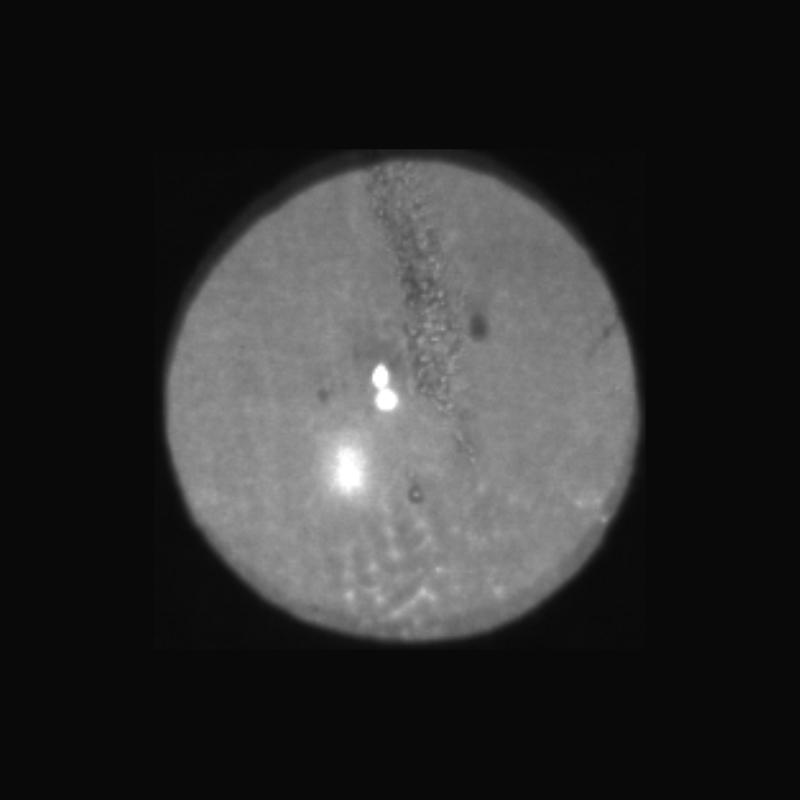

Netzhautbetrachtung

Mit unserer Funduskamera fotografieren wir den zentralen Bereich Deiner Netzhaut.

Hier verschaffen wir uns einen ersten Überblick über den gesundheitlichen Zustand des Sehnervs, der Macula, der Blutgefäße und der Netzhaut im Allgemeinen.